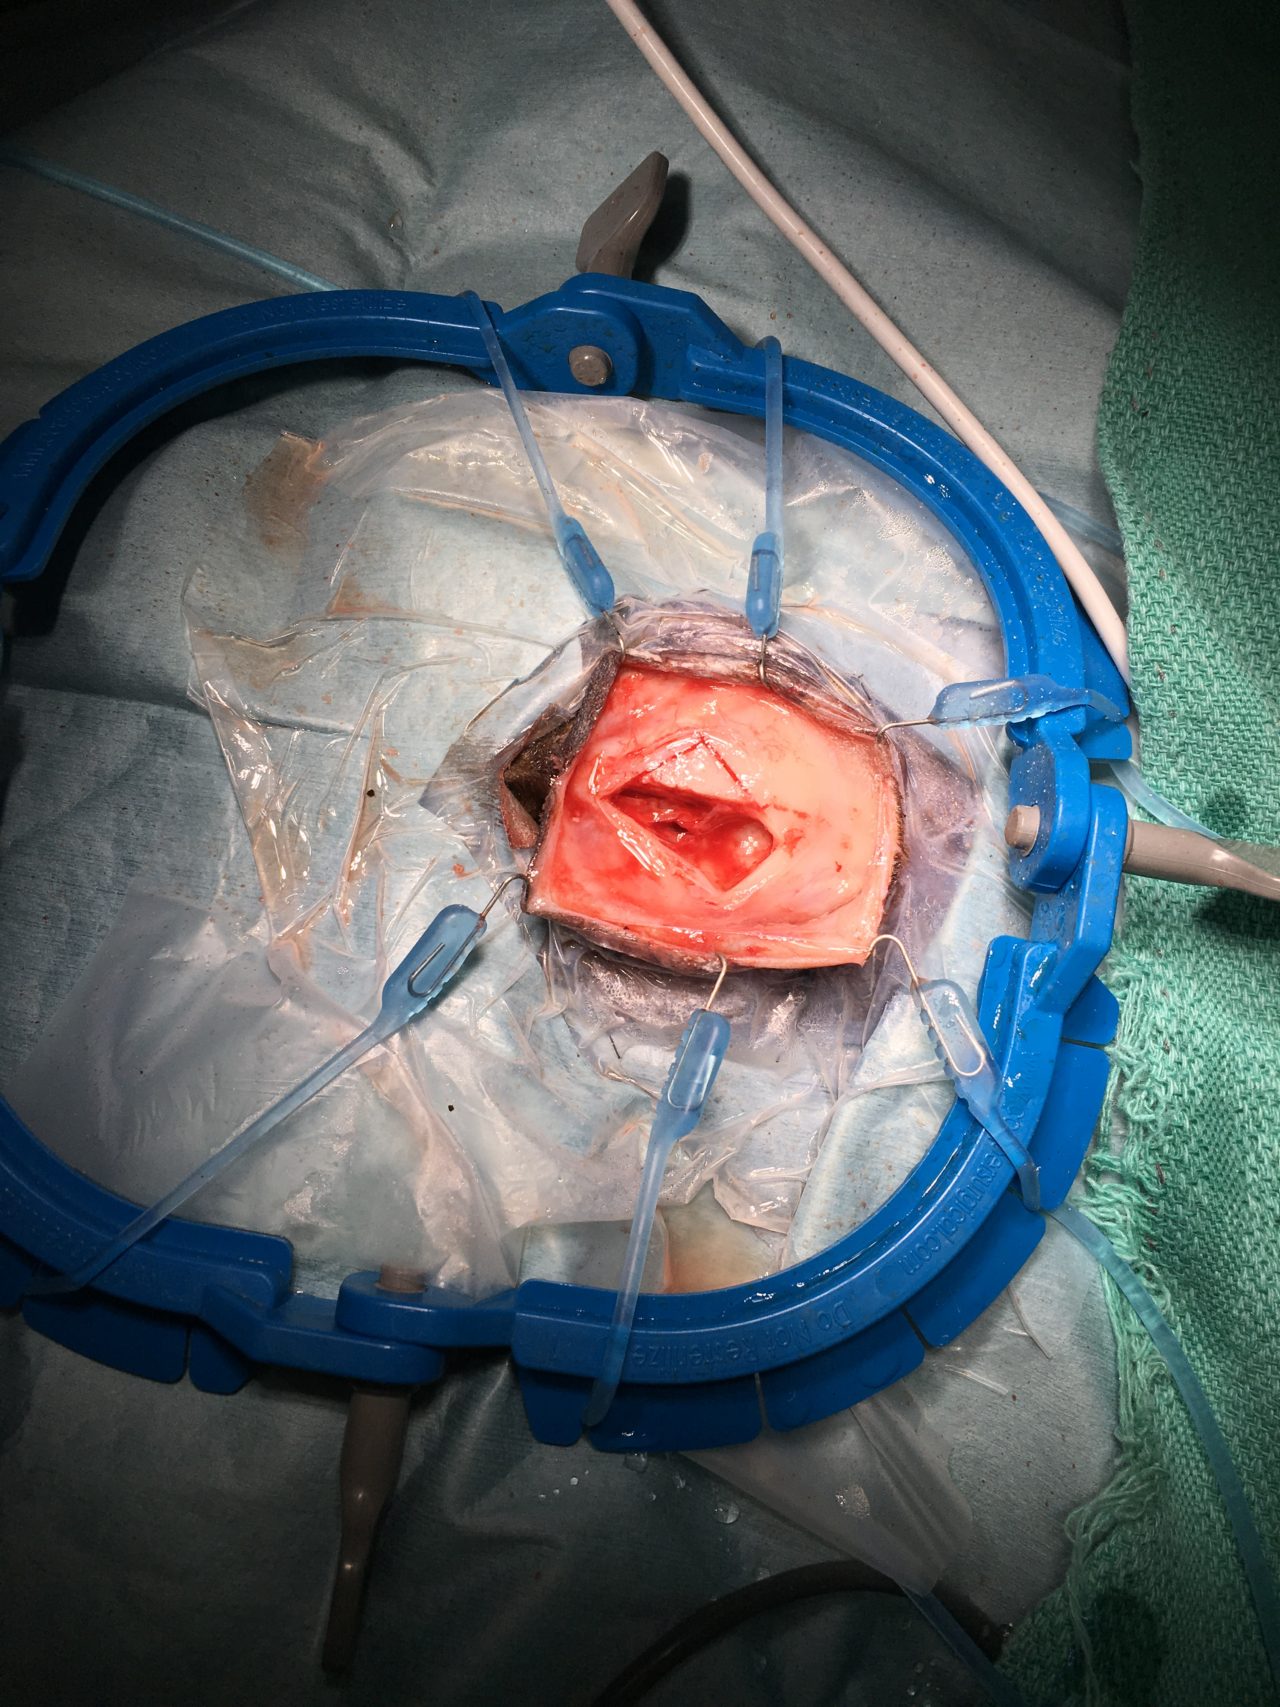

12歳の猫が2週間前よりふらつき、食欲不振、硬直性の痙攣があるとのことで、主治医から紹介がありました。MRIでは前頭葉を中心としたMASSエフェクトを伴う病変が確認されました。リンパ腫あるいは髄膜腫が強く疑われました。CSFでは無色透明で髄液蛋白60mg/dl、Ph8.5 細胞数2(5以下正常)単核球100%パンディ反応(+1)。CSF中のGlu63mg/dl、CK<10、Na 166 K 2.9 Cl 131。手術までの1週間の間にステロイドを中心とした内科療法を実施したところ、臨床症状も改善し、再度、実施したMRIでも以前の病変がほぼ消失していました。ステロイドに強く反応したことからリンパ腫の存在が強く疑われました。今後、化学療法を継続するか?否か?あるいはFIPなどの鑑別を行うために、嗅球と前頭葉の生検が行われました。生検の結果、コロナウイルスの感染、リンパ腫の存在は否定されました。また、血清学的にもトキソプラズマ、FIPの関与は否定的でした。そのため、プレドニゾロンを継続し、経過観察中です。2017年に猫のMUOについて世界で初めてイギリスより16例のまとまった報告が初めての論文として掲載されており、今回の患者さんはそのFMUOのカテゴリーに分類されると考えられました。